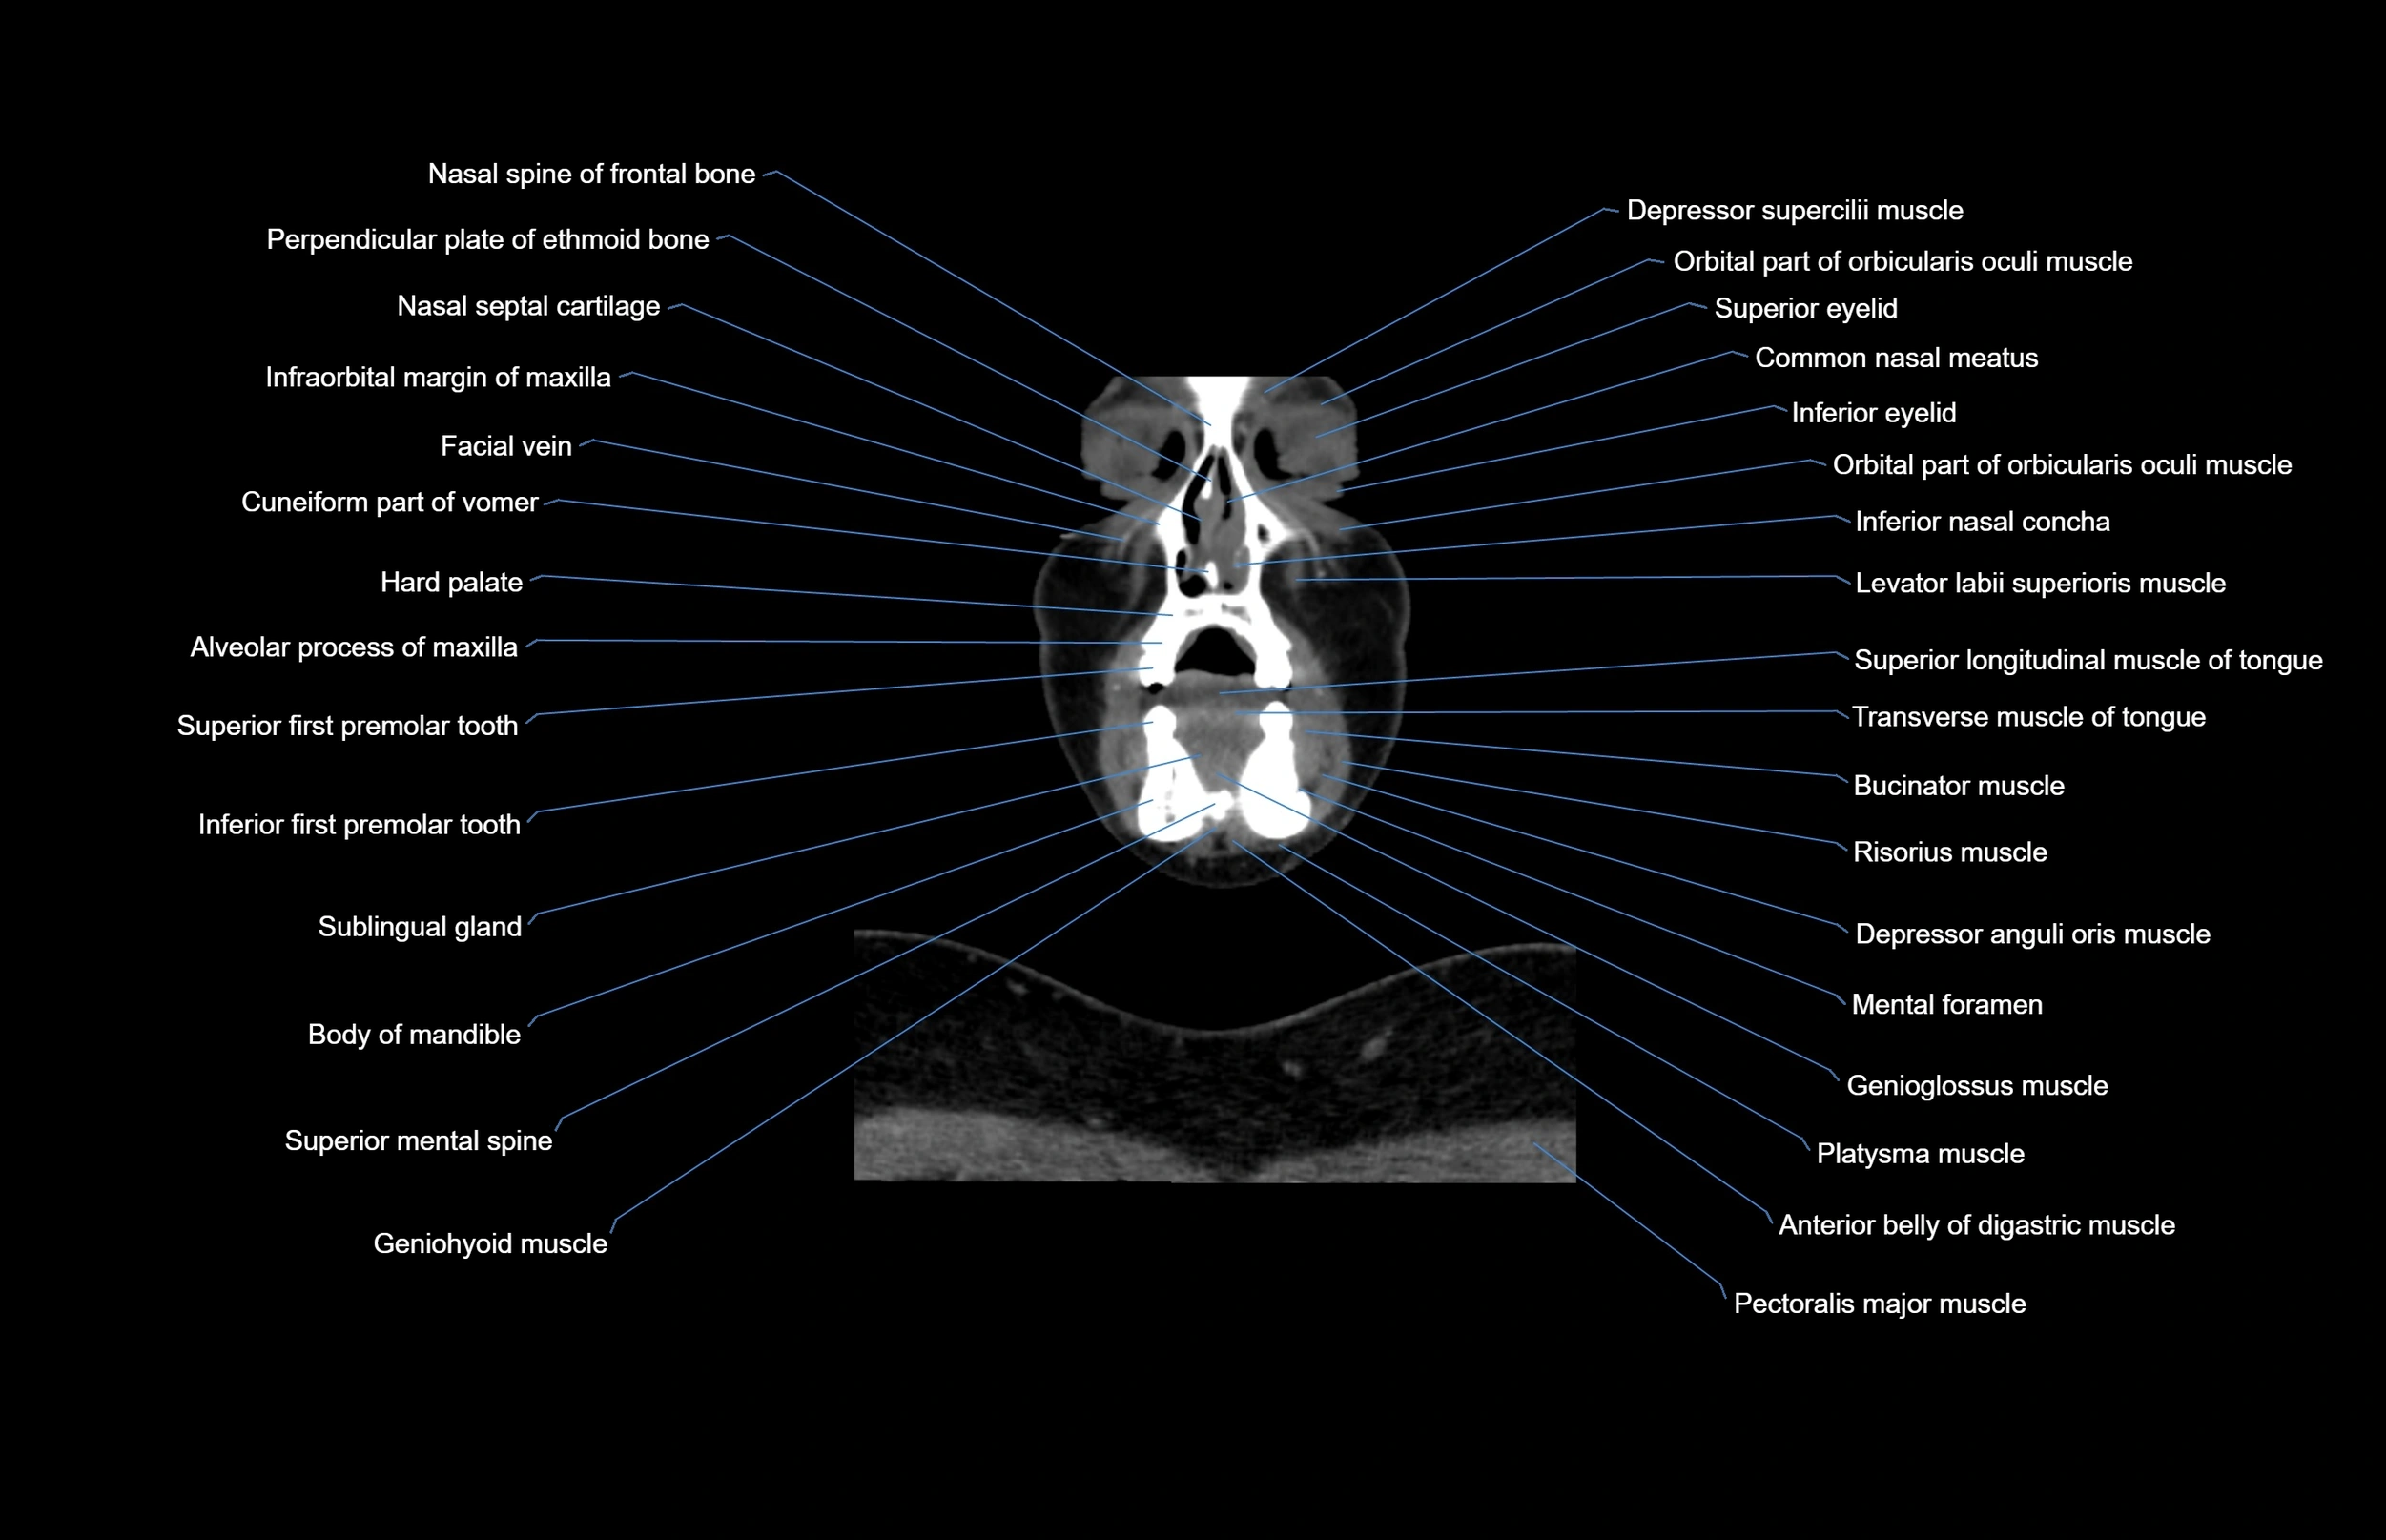

- Anterior belly of digastric muscle

- Facial vein

- Genioglossus muscle

- Inferior eyelid

- Inferior first premolar tooth

- Mental foramen

- Nasal spine of frontal bone

- Orbicularis oculi muscle

- Orbital part of orbicularis oculi muscle

- Sublingual gland

- Superior eyelid

- Superior longitudinal lingual muscle

- Transverse muscle of tongue